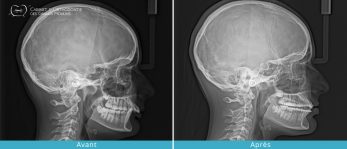

- Réduire les dysfonctions articulaires (craquements, douleurs, blocage, ) en améliorant l’occlusion dentaire et en corrigeant les décalages dentaires et squelettiques.

Ces traitements peuvent être complets, nécessitant parfois le recours aux extractions et/ou à la chirurgie maxillo-faciale ou partiels, dits « traitements de compromis ».

Dans certains cas et pour aider le traitement, des petites vis ou implants peuvent être mis en place afin d’avoir un ancrage solide pour déplacer les dents de façon plus efficace. Ces mini-vis ou mini-implants sont retirés à la fin du traitement et ne laissent aucune séquelle.